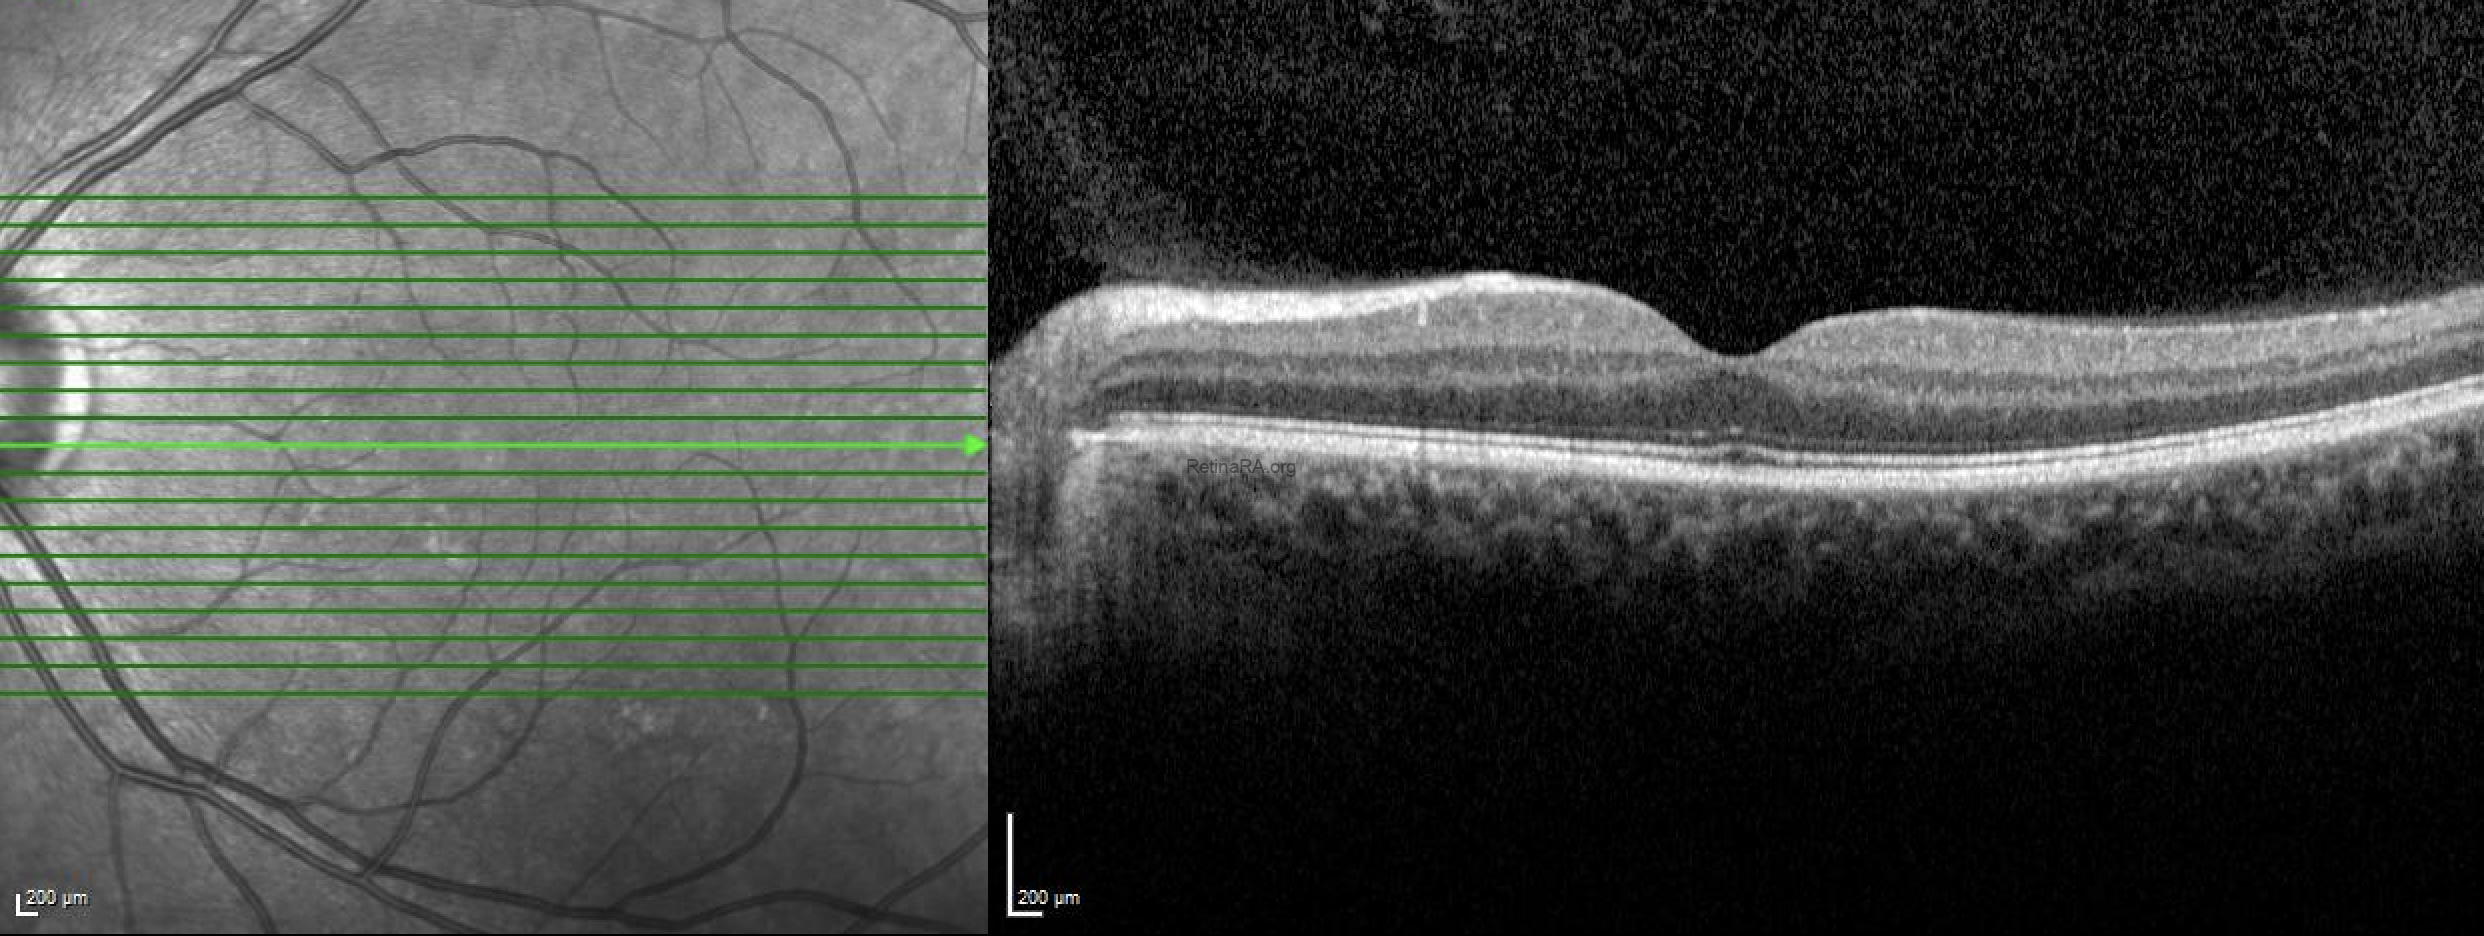

The quantiferon-TB test was positive and the patient was diagnosed with Tubercular serpiginous‑like choroiditis. Anti tubercular treatment (ATT) was started and then oral steroid was added. Healed lesions showed hypoautofluorescence on FAF.